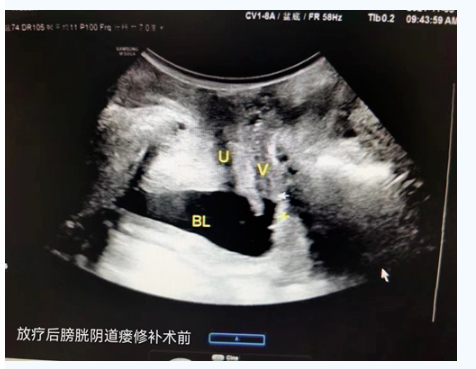

(2021-11-5)妇科B超示:盆底超声提示:前、中、后腔室:未见明显脏器脱垂,未见明显肛提肌及肛门括约肌断裂,肛提肌裂孔面积正常范围,妇科超声提示:膀胱阴道瘘,子宫萎缩。

(放疗后膀胱阴道瘘修补术前)